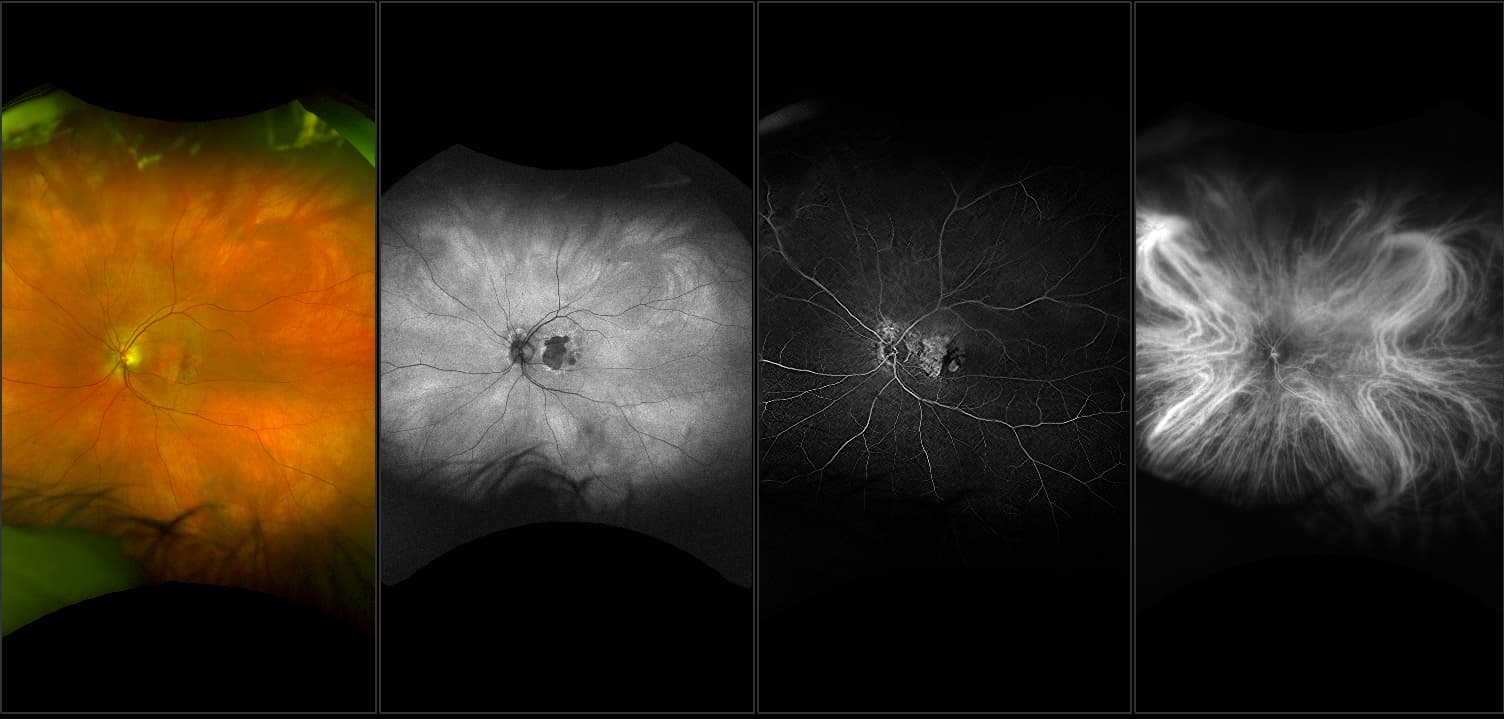

Acute multifocal placoid pigment epitheliopathy (AMPPE)

AMPPE affects otherwise young healthy adults and presents as a disorder affecting the retina, Retinal Pigment Epithelium and choroid. APMPPE is an acquired, self-limiting, inflammatory disorder.